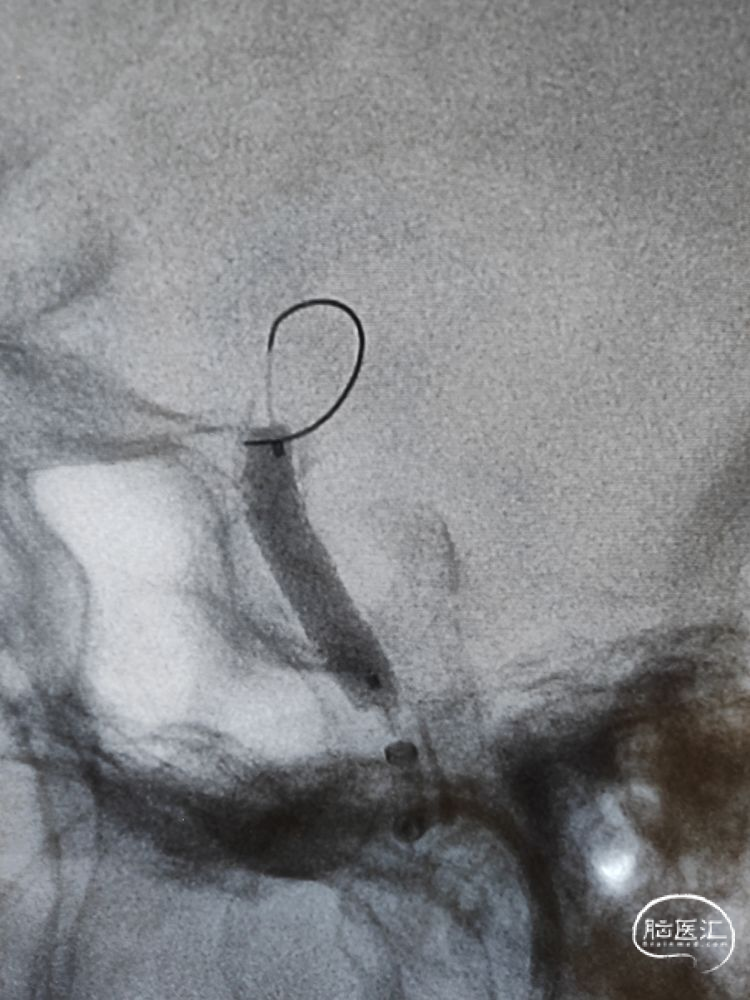

麻醉成功后,患者平卧位,双侧腹股沟区常规消毒、铺巾,取右侧腹股沟韧带中点下2cm处股动脉为穿刺点,采用Seldinger法穿刺成功,利用置换导丝置入8F鞘。选择侧位工作角度,在8F导引导管支撑下,将6F 115cm颅内支撑导管输送至海绵窦段接近狭窄近端建立稳定通路,大单弯塑形的0.014inch 200cm微导丝顺利通过狭窄段,换成正位工作角度将微导丝安全置于大脑中动脉M2段粗大分支平直段。